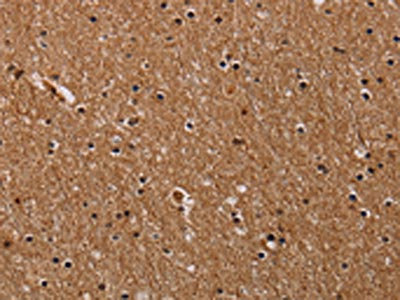

The image on the left is immunohistochemistry of paraffin-embedded Human brain tissue using CSB-PA148821(FABP3 Antibody) at dilution 1/40, on the right is treated with synthetic peptide. (Original magnification: ×200)